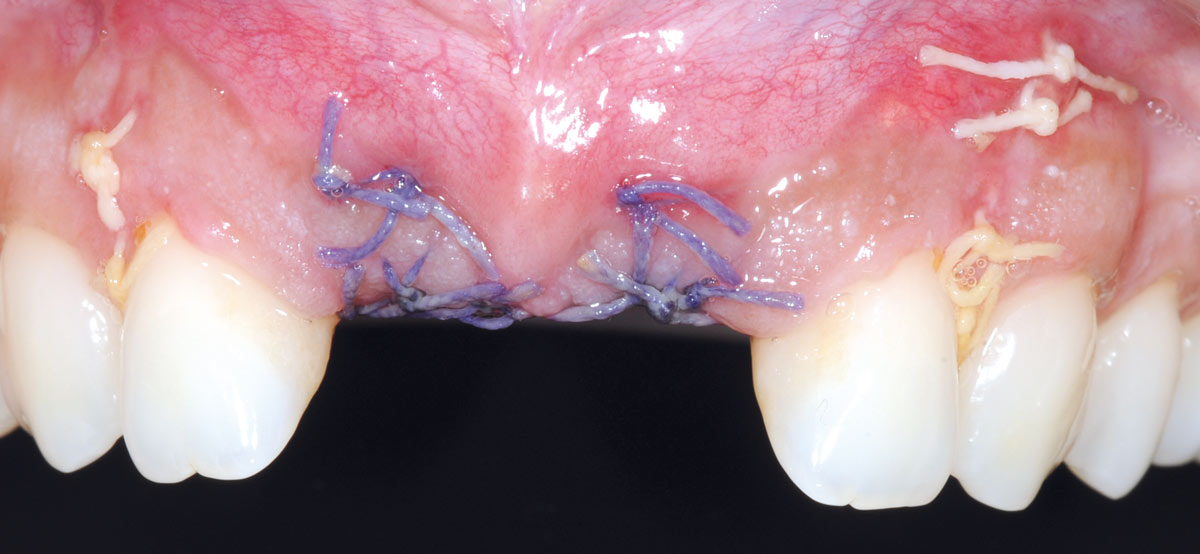

18/26 - Sutured free of tension with vycrilBone augmentation in aesthetic zone with maxgraft® bonering - Dr. A. Patel